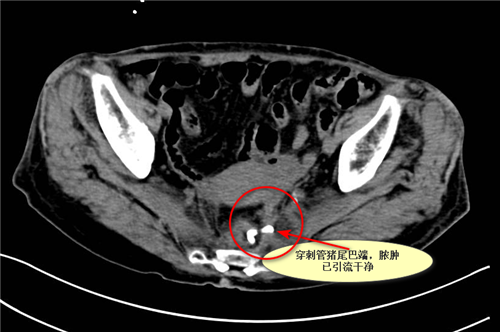

案例2.卞**,87岁女性,于上级医院行直肠癌根治术,因盆腔脓肿,反复腹痛伴发热10天收住胃肠外科,联系我科给予经直肠腔内超声引导下盆腔脓肿穿刺置管引流,引流当天体温即恢复正常。